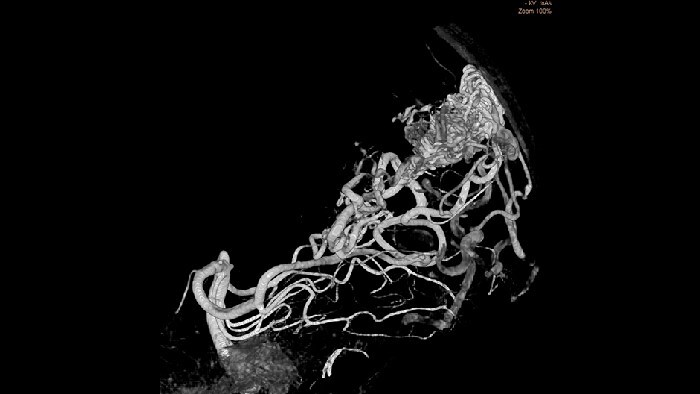

SmartCT Angio biedt binnen een paar seconden een volumetrische weergave ter ondersteuning van de beoordeling van aanvoerende slagaders, afvoerende aders, gearterialiseerde aderen, nidus en gescheurde of niet-gescheurde pathologie om de besluitvorming te geleiden. 3D-volumes worden gevisualiseerd met een hoge ruimtelijke resolutie en automatische compensatie van patiëntbewegingen om de zichtbaarheid van cruciale details te verbeteren.

De mogelijkheid om vasculaire anatomie van minder dan een millimeter te visualiseren vergroot de kans op slaging en verhoogt het vertrouwen in de behandeling. SmartCT Vaso biedt 3D-beeldvorming met een hoge resolutie die belangrijke informatie over vaatstructuren in de hersenen oplevert ter ondersteuning van de best mogelijke ruimtelijke beoordeling van de bloedvaten in een omgeving met weke delen.